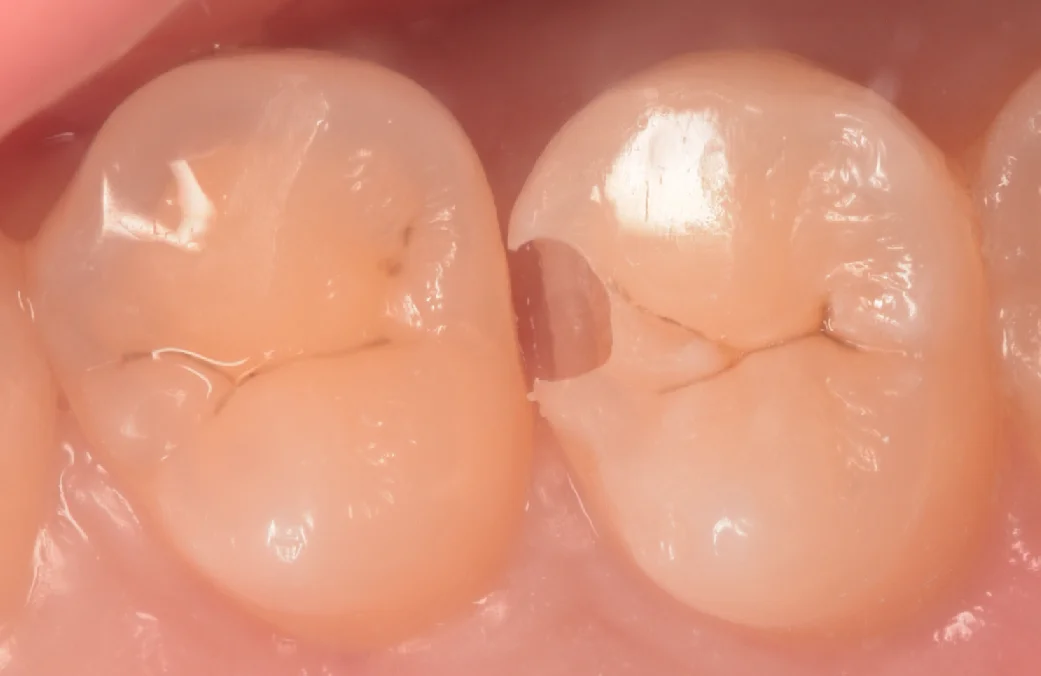

そして詰め終わったのがこちらになります。

歯の削る量を最小限にしている分、多少形に違和感があるかもしれませんが、機能的には全く問題はありません。

こちらの方は歯科医師ということもあり、小さい虫歯も自費で治すメリットをよくご存知の方でしたので自費で行いました。

基本的にはこのくらいのサイズであれば保険で行うことが多いですが、万全を期したい場合は自費での治療が無難となりますので、ご要望があれば予約の段階でお伝えください。

術前術後の比較写真がこちらになります。